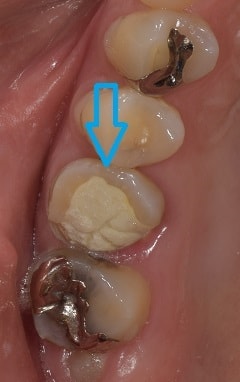

痛みの原因

青の矢印の歯が痛むと来られた患者さん。

この歯は、上顎第一大臼歯と言われる前から6番目の歯になります。

通常この歯の神経の通り道は、3本あり、約50%で4本あると言われています(もう少し高い確率であるよな気がしてます)。

あけてみると、案の定4本神経の通り道が。

赤の矢印で示しているものが、通常あると言われている3本の神経の通り道で、緑の矢印で示しているものが、4本目の神経の通り道になります。4本目の神経の通り道が、痛みの原因の全てではないですが、痛みの原因となりうるものを一つずつ改善していくことが、治癒につながるかと思います。